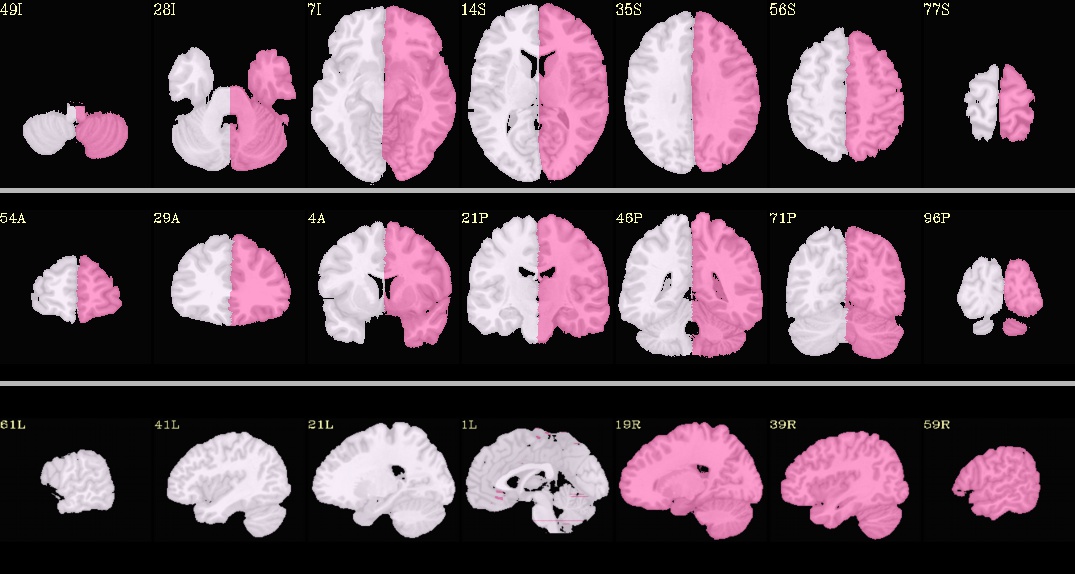

afni_refacer_MNIbmask10.nii.gz¶

Underlay: MNI152_2009_template_SSW.nii.gz |

afni_refacer_shell.nii.gz¶